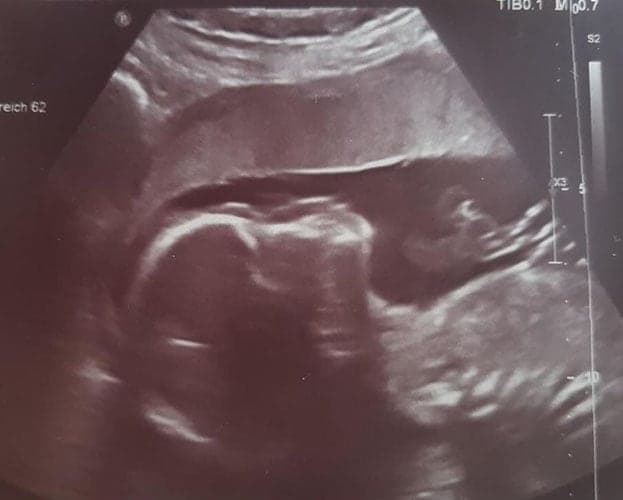

Ultraschallbilder aus dem 1. Trimester (1. SSW bis 12. SSW)

Im ersten Trimester sind die Ultraschallbilder meist noch schwer zu deuten. Oft erkennt man in den letzen Wochen des ersten Trimesters gut den Körper, den Kopf und die Gliedmaße. Das Geschlecht kann man in dieser Zeit meist noch nicht erkennen.